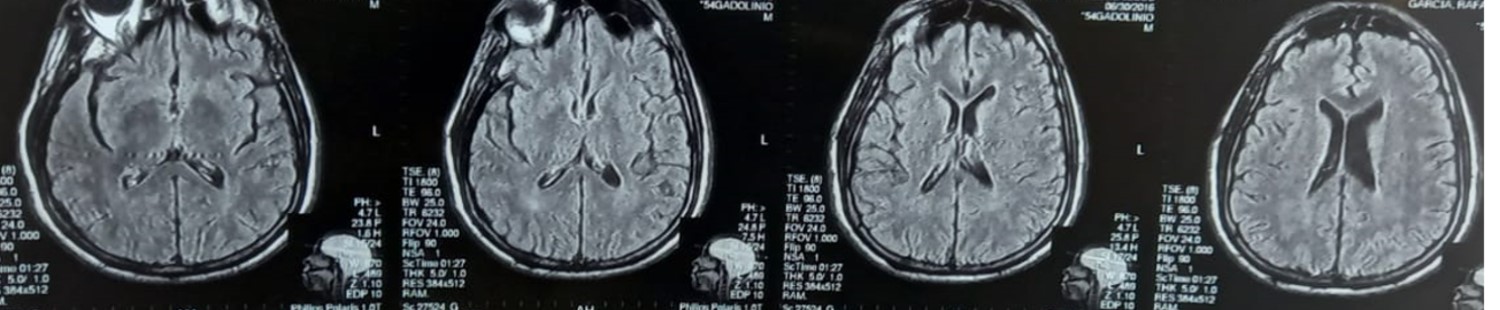

Results: It is important to highlight in the context of hypertensive crisis 3 years prior, a cranial magnetic resonance imaging had been performed without involvement of the nigrostriatal pathway. (Figure 2.) He was diagnosed with uremic striatopallidal syndrome. Furthermore, in the case of this patient, hyperparathyroidism secondary to kidney disease was taken into account as an aggravating factor. At follow up in our clinic 1 month later, he reported that the movements started to improve after optimized the hemodialysis therapy.

Figure. 2 MRI